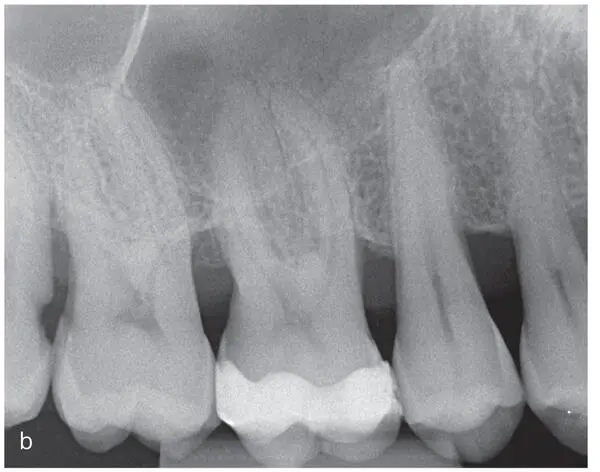

Figs 2-4a to fA 38-year-old (at time of admission) man with an inconspicuous general health and no medication. Diagnosis: periodontitis stage 4, grade C. This case continues in Fig 2-10. Baseline examinations: (a) first and fourth quadrants; (b) second and third quadrants; (c) frontal view; (d) maxillary arch; (e) mandibular arch; (f) baseline measurements of the clinical attachment level, including tooth migration and loosening, furcation involvement, and bleeding on probing (graphic illustration by Parostatus.de).

Figs 2-5a and bRadiographic examination of the patient introduced in Fig 2-3. (a) Panoramic radiograph and (b) intraoral radiographs. The radiographs show severe horizontal and vertical (locally) bone loss.